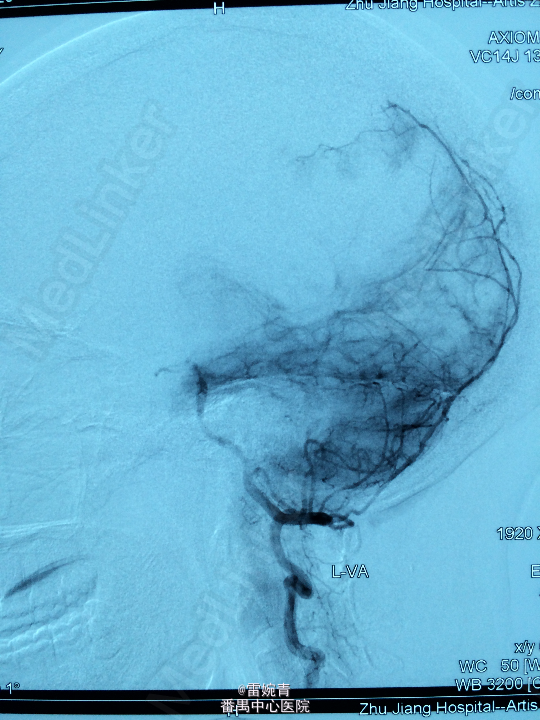

诊断:脑膜瘤 处理:先行DSA检查以明确脑膜瘤的供血动脉情况,见:肿瘤染色,肿瘤主要由左侧眼动脉供血,用Glubran胶将其闭塞,后择期行手术切除治疗。术后病理证实为脑膜瘤。

术后患者病情稳定,后出院。 讨论:脑膜瘤可由颈内颈外动脉双重动脉供血,血供较为丰富,直接开颅手术治疗出血量较多,如果能术前行介入栓塞治疗可减少书中出血量,并降低手术风险及难度。